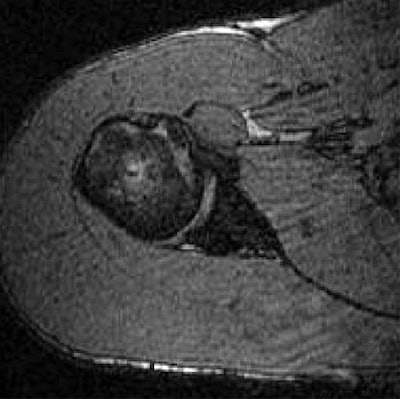

| Transverse 3D gradient-echo MR images (30/10) with volunteer in neutral position (above), unloaded ABER position at 90° external rotation (middle), and 111° external rotation (below). Note infraspinatus tendon (arrow) deformed between the greater tuberosity and posterosuperior glenoid in the loaded study. |

Based on the image evaluation, contact was observed between the supraspinatus and the posterosuperior glenoid in the unloaded and loaded ABER positions in all eight volunteers. Again, in all eight subjects, contact was noted between the infraspinatus near the insertion and posterior glenoid in the loaded and unloaded positions. Four cases were deemed grade 2. Intraobserver agreement between the two radiologists on supraspinatus and infraspinatus tendon contact with the glenoid was excellent (k = 0.875).

The researchers also assessed minimum distances and noted changes in distance in the loaded ABER position. They found that the minimum distance between the supraspinatus insertion and the acromion dipped from 16.9 mm to 5.7 mm, while the infraspinatus to glenoid distance went from 38.4 mm to 3.6 mm. The supraspinatus to glenoid distance went from 35 mm to 6.6 mm. Finally, the distance between the greater tuberosity and glenoid decreased from 21.5 mm to 3.6 mm.

This last result suggested that "a larger portion of the greater tuberosity (including the supraspinatus and infraspinatus insertions) may be important in the minimum distance measurement," the authors stated. "The infraspinatus insertion, in particular, came to within 3.6 mm from the glenoid, on average."

The group came up with a couple of recommendations based on the results. First, a decrease in minimum distance may not translate directly to clinical impingement because contact between the rotator cuff and glenoid occurs even in asymptomatic individuals during the loaded ABER position. Also, the loaded position may be more specific for internal, rather than subacromial, impingement.